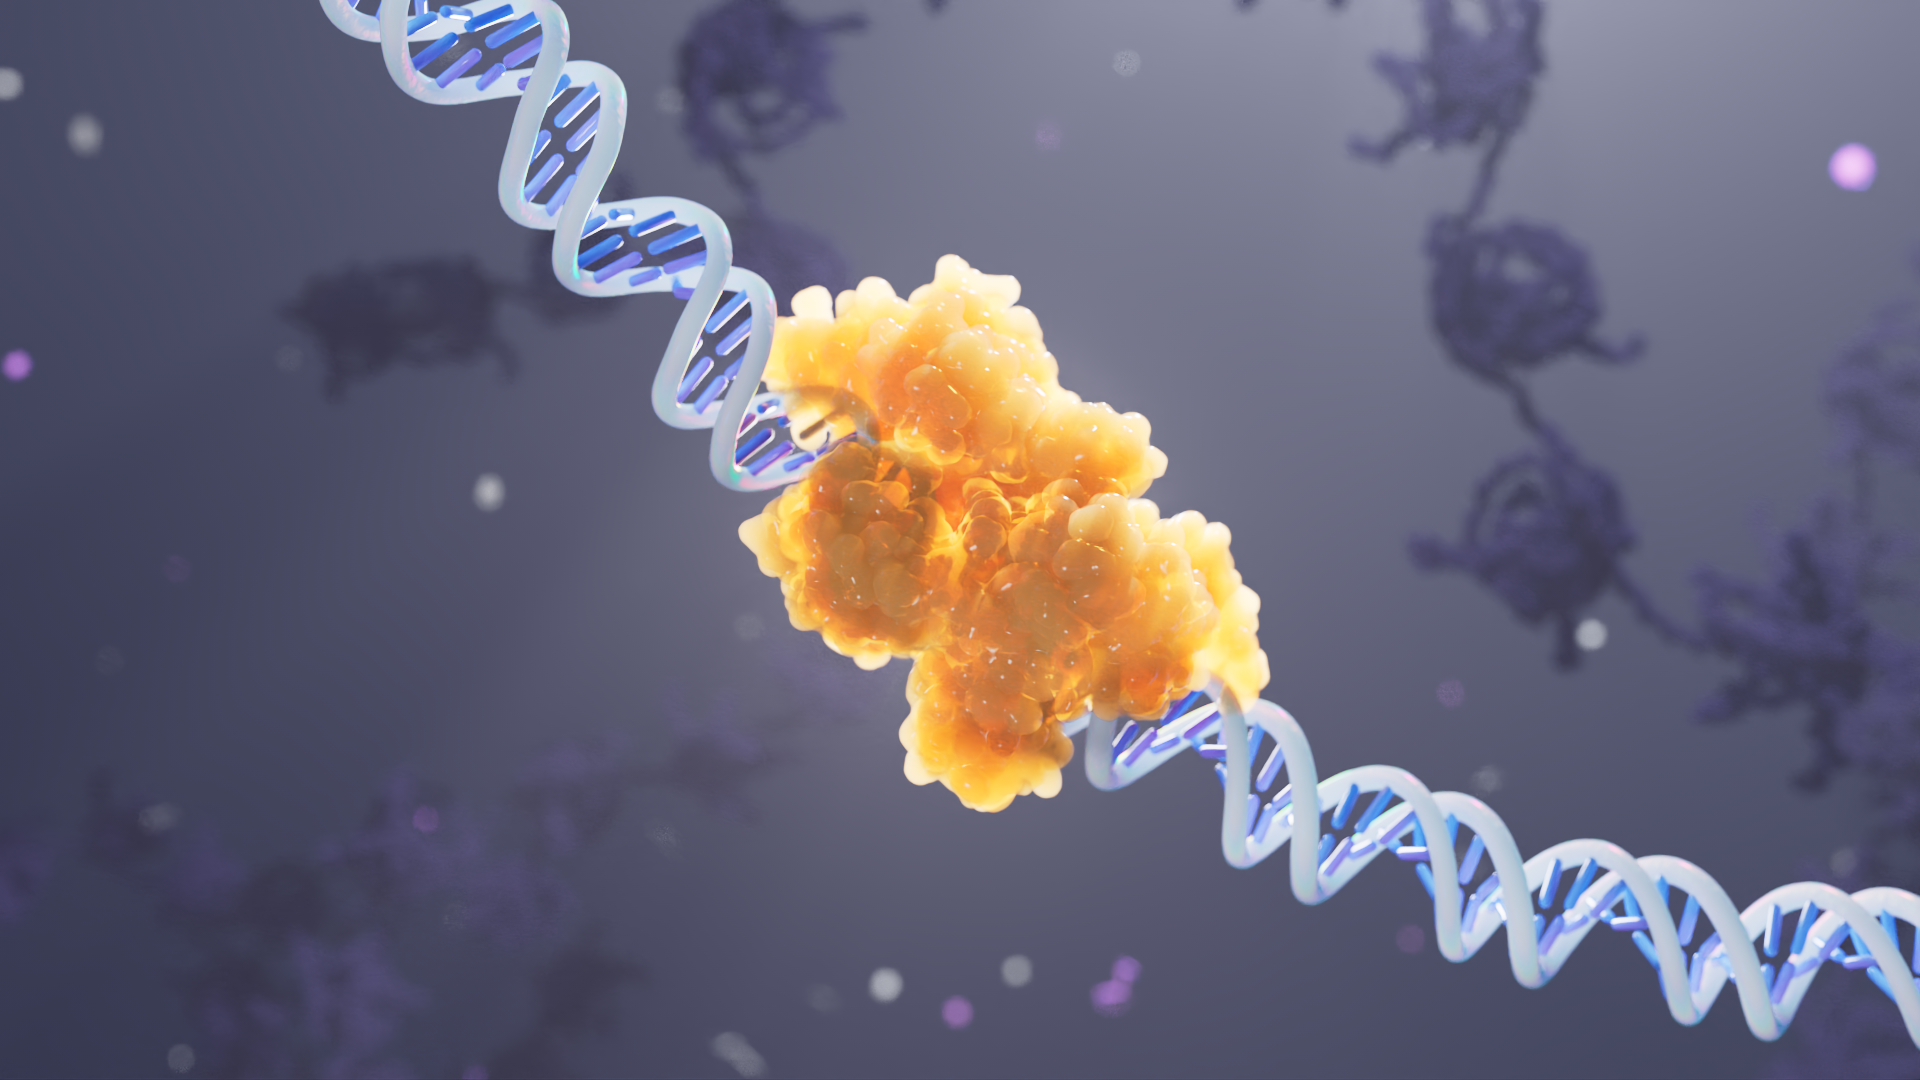

Genetic engineering

for the neuroscience revolution.

Empyrean Neuroscience is developing first-in-class, neuroactive therapeutics using genetic engineering to improve the lives of patients suffering from debilitating neuropsychiatric and neurologic disorders.

We developed an engaging 3D animation that details the “entourage effect”, a cascade of small molecules inherent to plants and fungi that work in concert to generate positive patient experiences and health benefits.

Style Frames